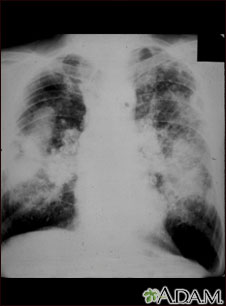

This picture shows complicated coal workers pneumoconiosis. There are diffuse, massive light areas that run together in the upper and middle parts of both lungs. These are superimposed on a background of small and poorly distinguishable light areas that are diffuse and located in both lungs. Diseases which may explain these X-ray findings include, but are not limited to: complicated coal workers pneumoconiosis (CWP), silico-tuberculosis, and metastatic lung cancer.